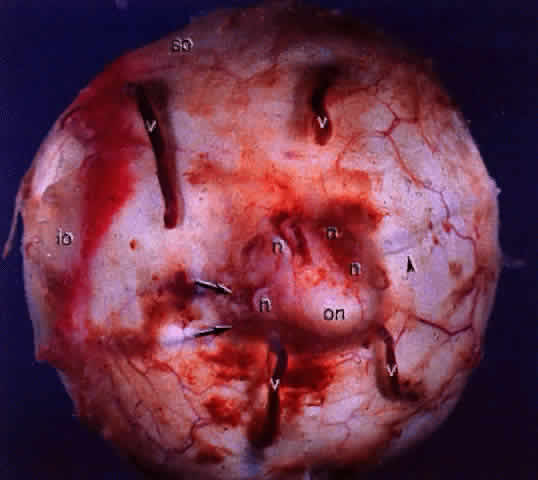

Fig. 14. Gross specimen of posterior of globe shows many of the structures shown

in Fig. 13: vortex veins (v), optic nerve (on), muscular tendon of inferior oblique (io), tendon of superior oblique (so), short posterior ciliary arteries (arrows), short posterior ciliary nerves (n), and long posterior ciliary artery and nerve (arrowhead). Fig. 14. Gross specimen of posterior of globe shows many of the structures shown

in Fig. 13: vortex veins (v), optic nerve (on), muscular tendon of inferior oblique (io), tendon of superior oblique (so), short posterior ciliary arteries (arrows), short posterior ciliary nerves (n), and long posterior ciliary artery and nerve (arrowhead).